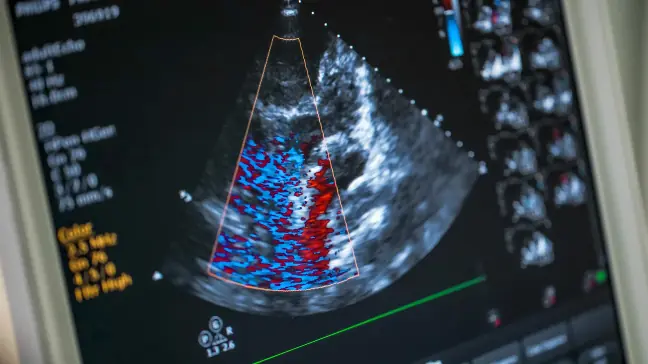

اکوکاردیوگرافی یک روش تصویربرداری است که از امواج صوتی برای تولید تصاویر زنده از قلب استفاده می‌کند. این تصاویر به پزشکان کمک می‌کند تا مشکلات قلبی را تشخیص دهند و درمان مناسب را تجویز کنند.

در اکوکاردیوگرافی، پروب بر روی قفسه سینه بیمار قرار می‌گیرد و امواج صوتی به قلب فرستاده می‌شود. این امواج پس از برخورد با ساختارهای قلب بازتاب می‌یابند و تصاویر زنده‌ای از قلب را بر روی صفحه نمایشگر نشان می‌دهند.